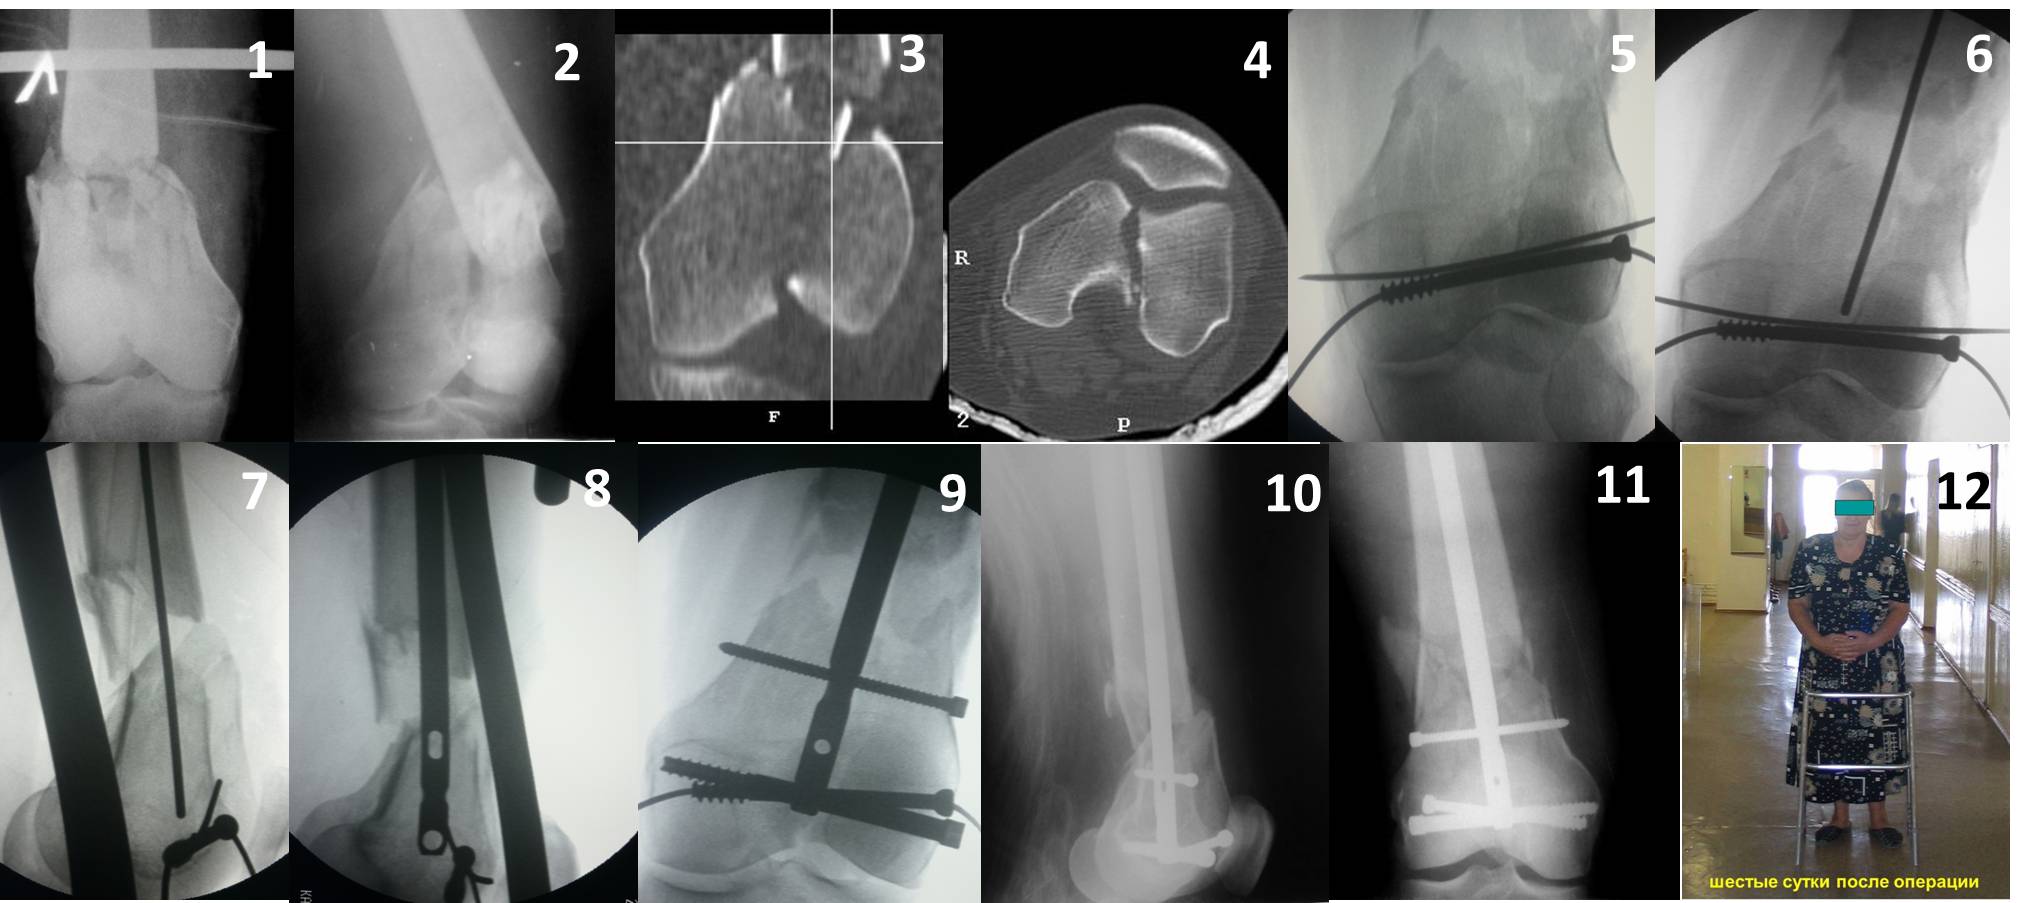

У больных как в этом случае, с вовлечением двух мыщелков правильно, что сделали вытяжение до операции. Здесь имеется флексионный компонент на другой стороне, и я бы рекомендовал операцию делать из двух доступов. Сперва фиксировать медиальную колонну custom made пластиной, обычно 1/3 тубулярной пластиной в 4.5 мм, потому что пока производители опаздывают с медиальной пластиной.

Пластину надо устанавливать на апексе перелома, иначе фрагмент начнет сползать. А на второй стороне, если имеется большой одиночный фрагмент тогда проблем не бывает, и их можно собрать компрессирующими винтами. Проблема наступает тогда когда многофрагментраность на латеральной стороне, где надо применить комбинированный метод, иногда несколькими пластинами. Или сменой позиции установки пластины, чтобы максимально прикрыть перелом и создать боковую поддержку.

Здесь пример медиальной пластины и латеральный комбинированный метод (у второго больного старый перелом тибиал плато, леченный где то и когда то)